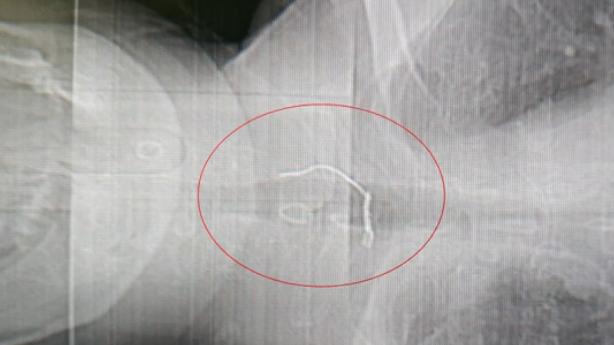

在瑞金医院北院手术室里,医生正在取出的是一根铁丝。就是这根小小的铁丝,被胡老伯误以为是梅干菜。医学影像资料显示,整根铁丝长约6厘米,呈L形,其中有2厘米已经穿过食管壁。

如果不及时取出,一旦食管壁撕裂、伤口感染发炎,可能会危及生命。医生最后通过胃镜下食管异物取出术,将铁丝拿了出来。

由于铁丝较长、且造型奇特,稍有不慎就可能取不出来。为以防万一,医院第一时间为胡老伯开通了绿色通道,一旦胃镜取物失败,就要进行开胸手术。